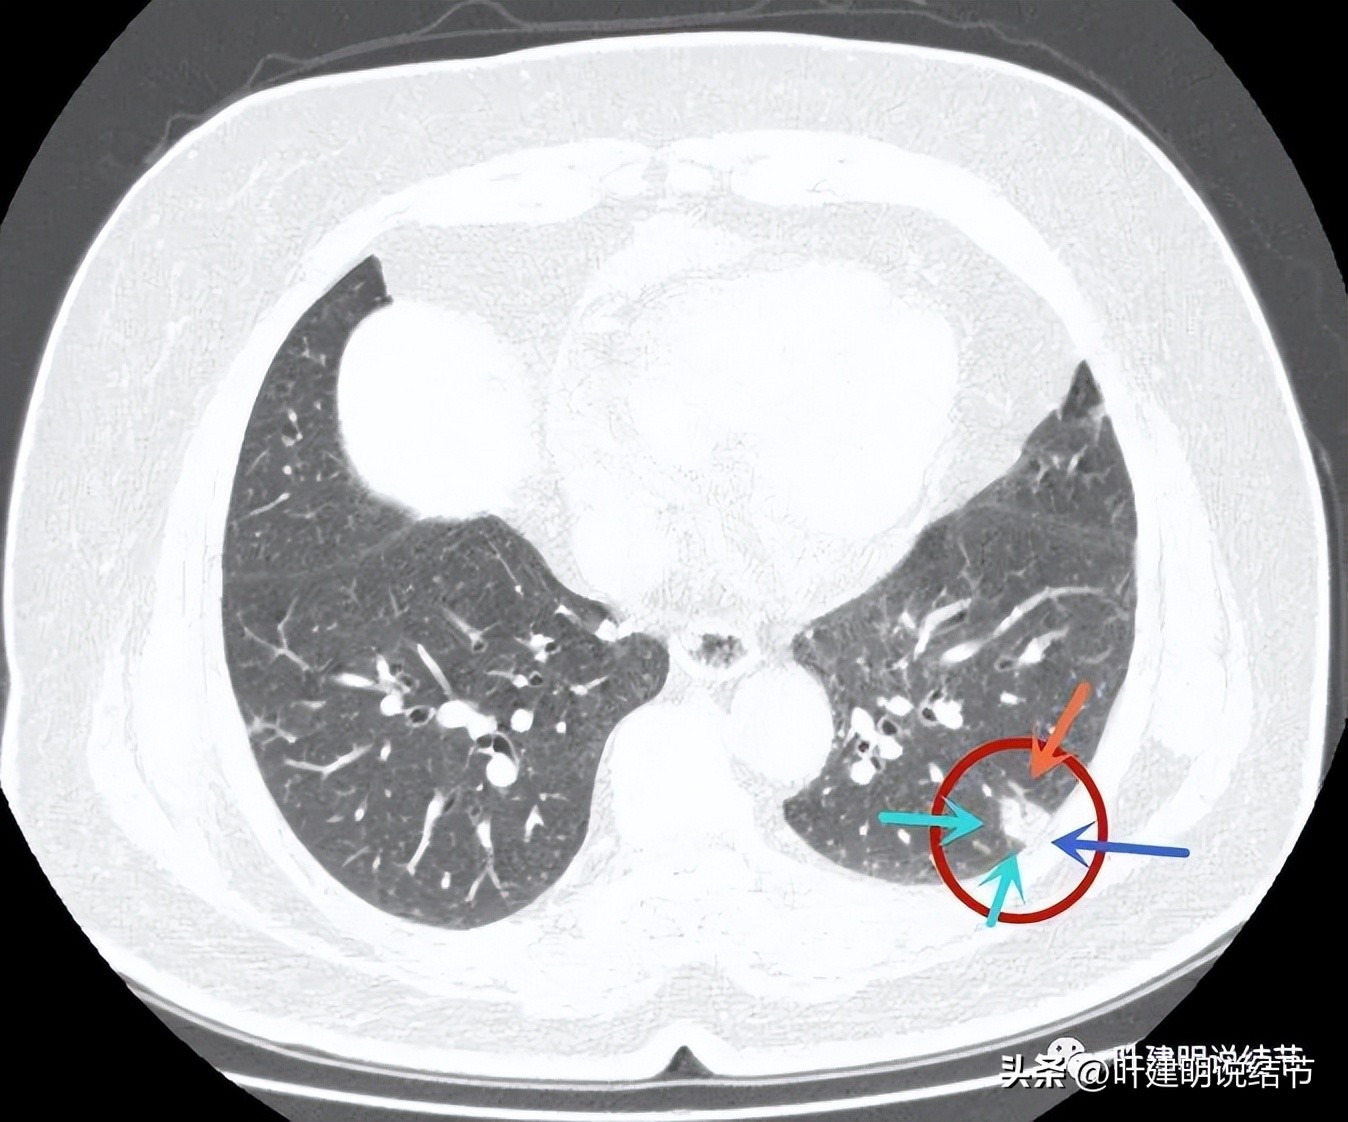

病灶表面不是很平整,整体密度较高,胸膜间隙征存在。

病灶有血管进入,但血管是逐渐变细的,不是异常增粗。而且病灶的几条边都比较平直,缺乏膨胀性。与胸壁也是紧贴,没有造成牵拉或侵犯影响。

边缘平直,血管进入变细

边缘平直似梯形

与胸壁接触的面较宽,余边也平直。